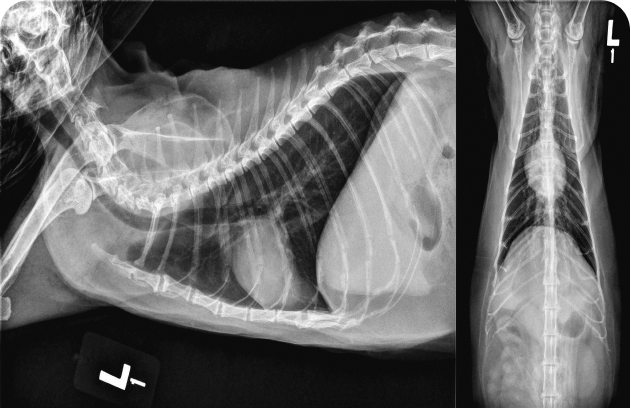

У котят шумы в сердце обнаруживают относительно часто, и при их диагностике и лечении врач должен придерживаться систематического подхода. Решающую роль в определении следующих шагов играют тщательный сбор анамнеза и тщательное клиническое обследование. Рентгенография грудной клетки может быть полезна при первоначальном обследовании, но для установления окончательного диагноза причин шума требуется эхокардиография; показанием к ее проведению считают шумы IV степени или выше, либо клинические признаки по результатам физикального осмотра. Терапию определяют исключительно на основании окончательного диагноза.